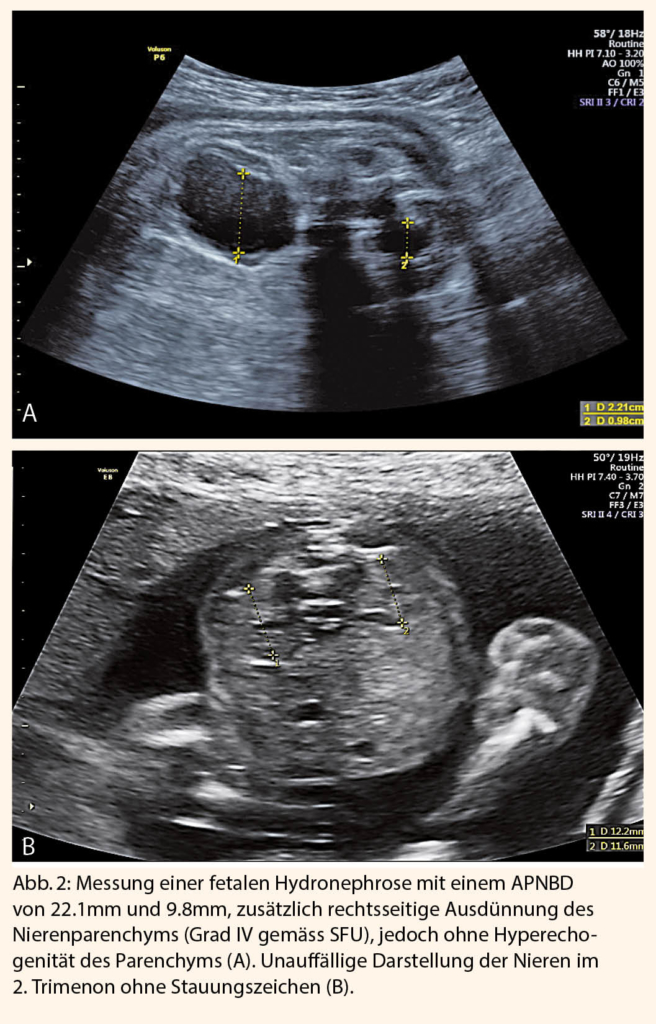

Eine zusätzliche Erweiterung der Nierenkelche spricht für eine fortgeschrittene Hydronephrose (Hydronephrose Grad II und III gemäss SFU). Hierbei ist wichtig, eine Verbindung zwischen Kelchen und Nierenbecken darzustellen, um die Erweiterung der Nierenkelche von Nierenzysten zu unterscheiden. - Ausdünnung und Echogenität des Nierenparenchyms

Eine Ausdünnung des Nierenparenchyms entspricht der maximalen Dilatation der Nierenkelche (Grad IV gemäss SFU).